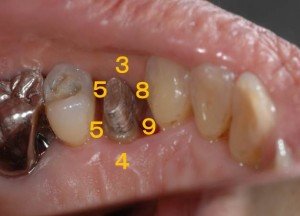

被せ物を外して土台の状態です。歯周ポケット検査は、手前(8mm、9mm)と奥側(5mm、5mm)です。要は、歯と歯の間から歯周病が進行してしまっています。